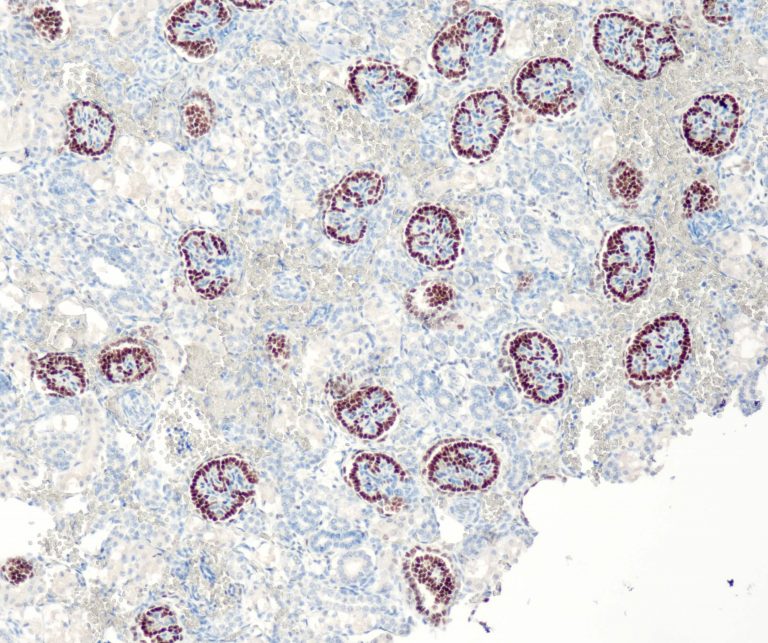

Urinary Tract Pathology